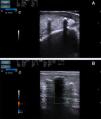

A, Ultrasound image. B mode: sagittal section showing increased thickness and decreased echogenicity of the dermis, compatible with inflammation, and hyperechoic deposits with a linear morphology that produce an acoustic shadow. The deposits are located in the dermis and in the subcutaneous cellular tissue. B, Ultrasound image. Doppler study: absence of flow.

On physical examination, both legs were indurated and presented hyperpigmentation (Fig. 1A) with hard, well-defined subcutaneous nodules over which there were brownish-erythematous macules with a reticular pattern (Fig. 1B). The blood tests gave the following results related to her underlying disease: hemoglobin, 10.7mg/dL; creatinine, 1.8mg/dL; urea, 119mg/dL; sodium, 138mmol/L; potassium, 4.7mmol/L; parathyroid hormone, 114pg/mL; calcium, 9mg/dL; phosphorus, 3.7mg/dL. Ultrasound study (Esaote My Lab One with a variable frequency linear array of 18-22MHz with a lateral resolution of 240μm) demonstrated a thickened and hypoechoic dermis, suggestive of inflammation, and hyperechoic deposits with a density similar to bone and with a linear morphology. These deposits were located in the dermis and in the subcutaneous cellular tissue and left an acoustic shadow (Fig. 2A). Flow was absent on Doppler study (Fig. 2B). Skin biopsy revealed fibrotendinous tissue with mature cartilage (Fig. 3).